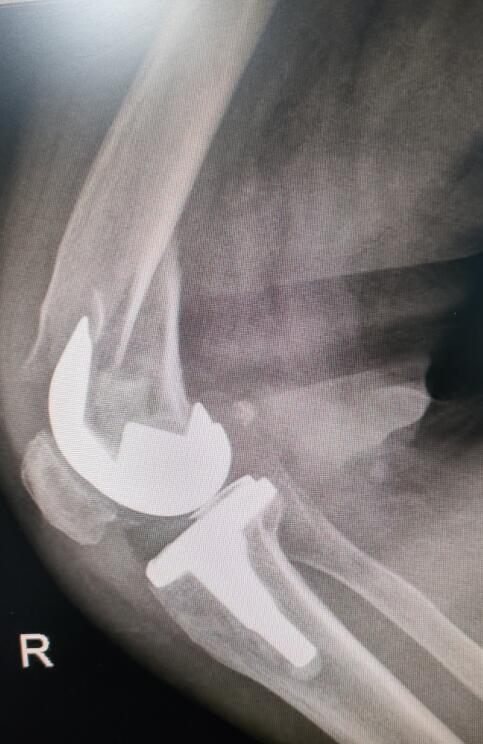

手術后照片